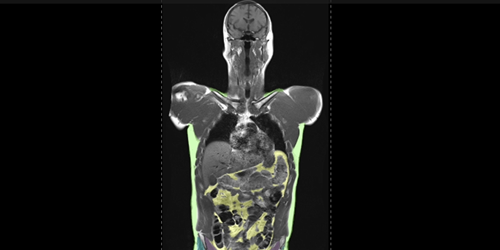

For the ongoing study, 1,164 healthy individuals (52% women) from four sites were examined with whole-body MRI. The mean chronological age of the participants was 55.17 years. The researchers combined MRI imaging with T1-weighted sequences, a technique that produces images where fat appears bright and fluid appears dark. This allows for optimal imaging of muscle, fat and brain tissue. An artificial intelligence (AI) algorithm was used to quantify total normalized muscle volume, visceral fat (hidden belly fat), subcutaneous fat (fat under the skin) and brain age.

Video 1: Body MRI shows the results of the AI approach in a de-identified research participant with color-coded segmented muscle and fat metrics that allowed study investigators to compute visceral fat and total muscle volume across the entire study. Light green color on this video is subcutaneous fat, yellow is visceral fat, brown are the thigh muscles, purple are the psoas muscles, and dark green are the gluteal muscles.